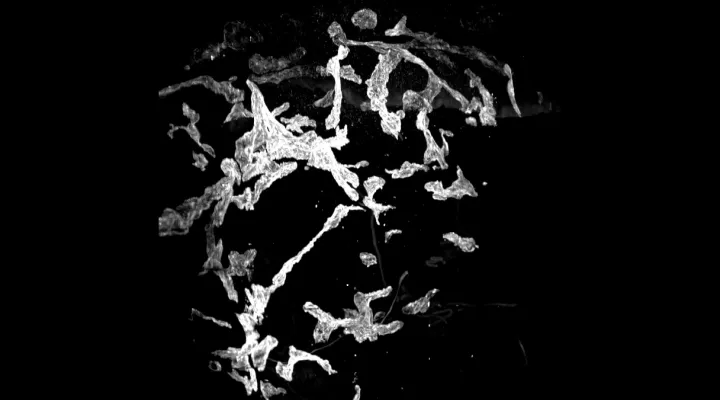

Lymphödematöse Haut

3D-Rekonstruktion der lymphatischen Gefässstruktur einer lymphödematösen Haut. Sie zeigt gestörte und nicht verbundene lymphatische Gefässe.